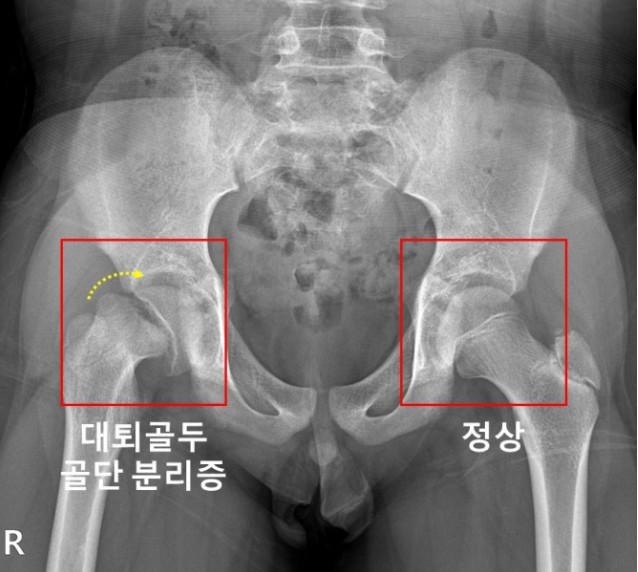

대퇴골두 골단 분리증은 대퇴골 위쪽 성장판 부위에서 대퇴골두와 그 아래의 뼈가 특별한 외상 없이 분리되는 병이라고 합니다. 진단이 지연될 경우, 대퇴비구 충돌증후군 혹은 대퇴골두가 썩는 대퇴골두 무혈성 괴사가 발생할 수 있다고 합니다.